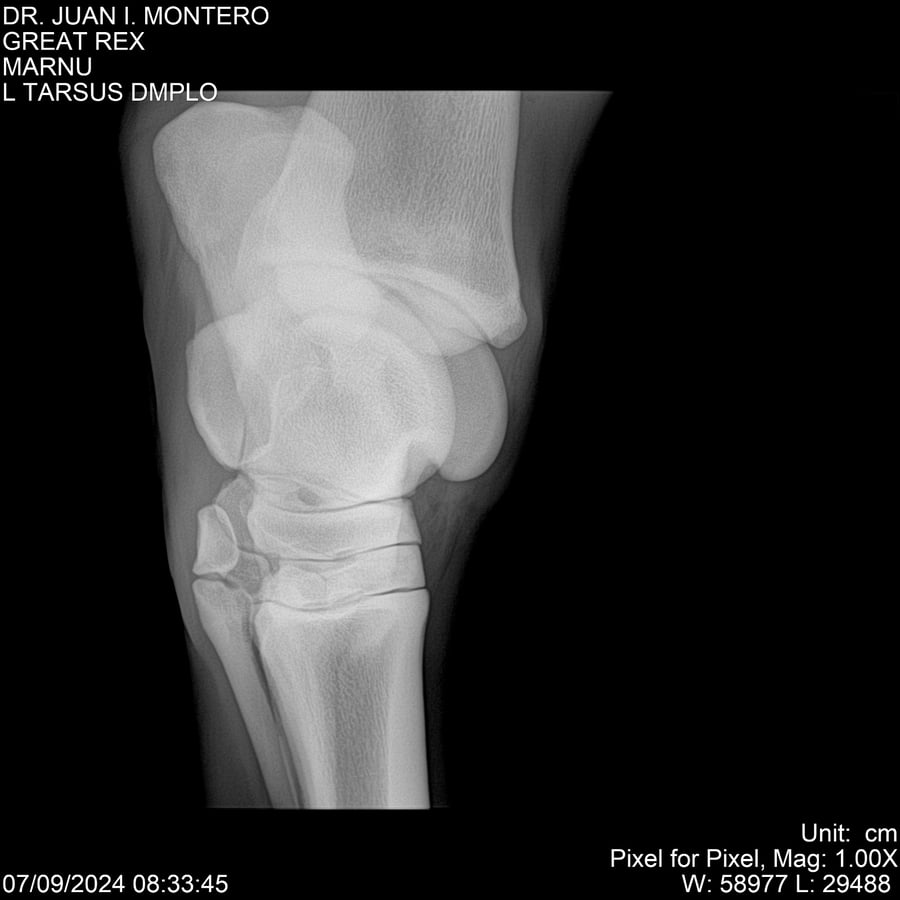

LOTE 4, GREAT REX Lote Anterior Volver al remate Lote Siguiente Ficha Contacto Montevideo - Ficha del Lote Identificador: #282518 Categoría: Yeguarizos Montevideo - 66 Visualizaciones ClicData Contacto Empresa: Abelenda N. R., Walter Hugo Nombre*: Teléfono* : E-mail* : Mensaje Enviar Registrese gratis Este contenido Exclusivo está disponible sólo para usuarios registrados Ingresar